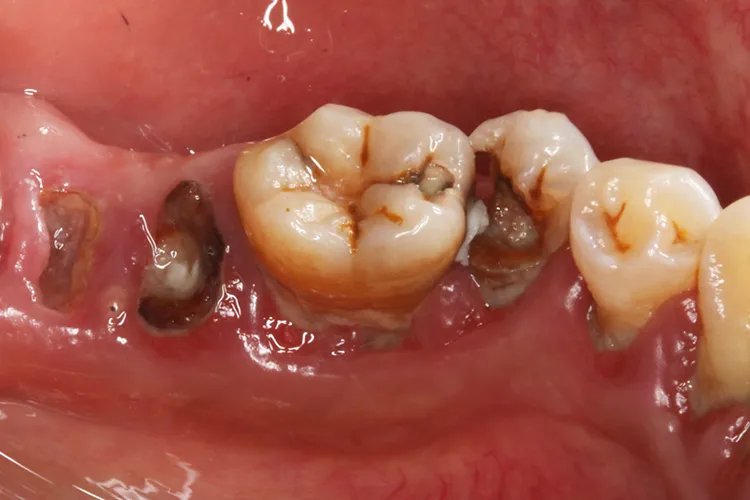

外形缺损是龋齿最显著的临床特征,形成了牙体组织的实质性缺损。临床上可以看到、探到或检查到龋洞。

质地的改变龋造成的牙体组织的实质性缺损称为龋洞。龋洞中充满感染脱矿的牙体组织和食物碎屑,质地松软,容易与正常组织区别。

患者感觉的变化当龋损发展到牙本质层并出现龋洞时,才有冷热刺激或食物崁塞时的敏感症状,但都是一过性的,刺激消失,症状随之消失。当龋发展至牙本质深层时,症状会明显一些。病因发生龋齿的原因主要是由于具备了致龋菌和致病的牙菌斑环境,同时口腔中含有细菌代谢的底物,当酸或致龋物质聚集到一定浓度并维持足够时间时,就会发生龋。诊断龋齿的诊断以患者对患牙的感觉为基础,对患牙进行检查。使用不同型号不同大小的探针,可以发现早期的窝沟龋和发生在邻面的龋。在视诊和探诊不能确定龋损的情况下,应拍摄X片。光学检查、电导检查、龋损组织化学染色等对龋齿的诊断也有一定的作用。治疗龋齿的治疗应对个案进行分析,制定治疗计划。考虑患者目前的主要问题,及时终止病变的发展,做好预防和保护。对于已经有龋洞应尽可能去除坏死组织,封闭龋洞,修复龋损,恢复功能。